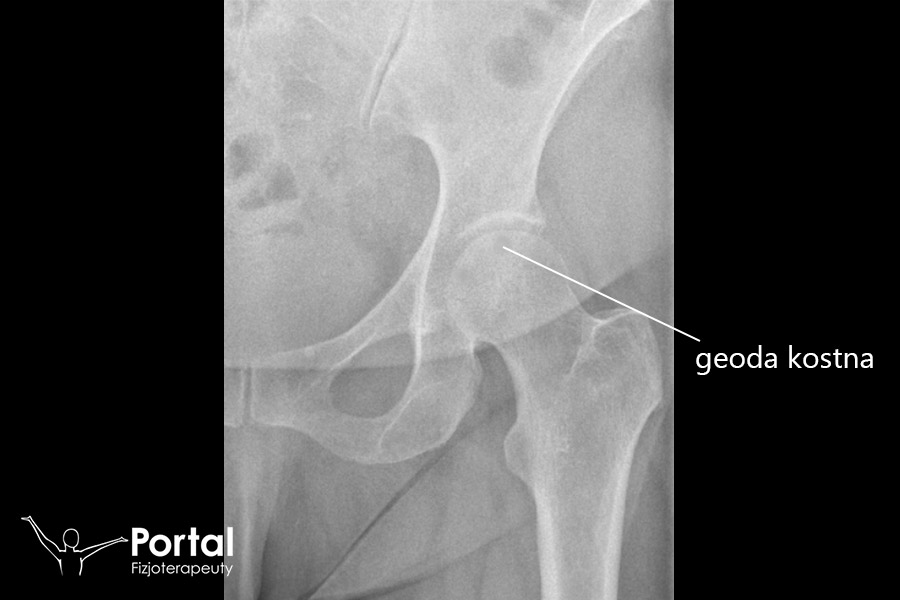

Geoda kostna to inaczej torbiel zwyrodnieniowa. W przebiegu niektórych chorób reumatycznych w tkance kostnej tworzą się różnej wielkości okrągłe ubytki, […]